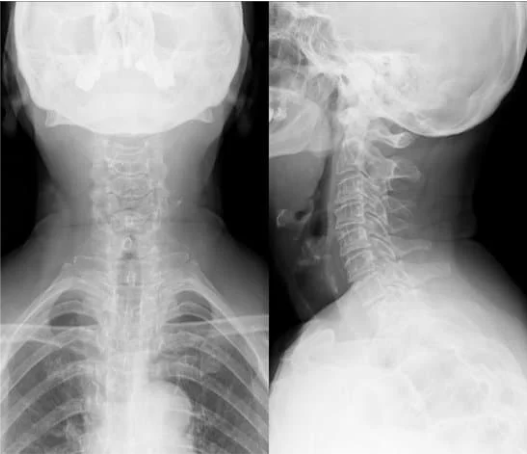

まずレントゲンを撮像し、正面と側面、顎を引いた状態、顎を上げた状態での頸椎の骨の並びや動揺があるかを評価し診断を行います。

首の痛みが悪化しない範囲で撮影しますので、ご安心ください。

レントゲンで骨と骨の隙間が狭くなっていたり、骨がずれているなどの変性所見(加齢性の変化)があると頚椎症を考えます。